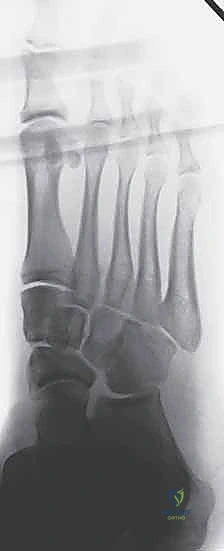

2. التصوير بالأشعة السينية (X-Rays) مع تحميل الوزن

الأشعة السينية العادية قد لا تظهر الإصابة إذا لم تكن العظام مزاحة بشكل كبير. السر يكمن في طلب أشعة سينية أثناء وقوف المريض وتحميل وزنه على القدم المصابة (Weight-bearing X-rays).

* يبحث الدكتور هطيف عن "علامة الفليك" (Fleck Sign)، وهي قطعة عظمية صغيرة مكسورة ومسحوبة من قاعدة المشط الثاني أو العظم المسماري الإنسي، وهي دليل قاطع على تمزق رباط ليزفرانك.

* كما يتم قياس المسافة بين قاعدة المشط الأول والمشط الثاني. أي اتساع يزيد عن 2 ملم يُعتبر غير طبيعي ويشير إلى عدم الاستقرار.